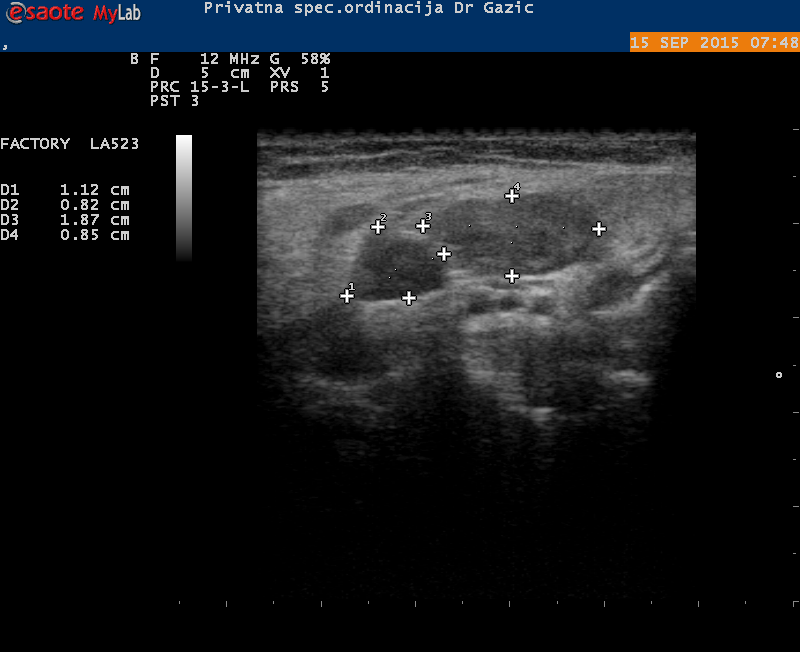

Štitna žlijezda - Bolest savremenog doba